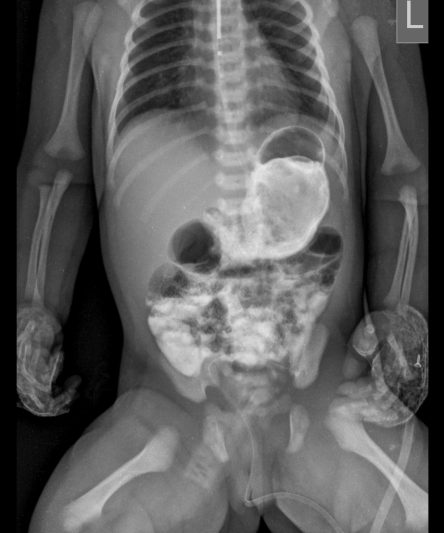

Microskan with Ultra high frequency can take the Lateral Lumbar Spine image of a 90 kg Patient with the correct image receptor

Microskan is the lightest mobile X-ray unit available